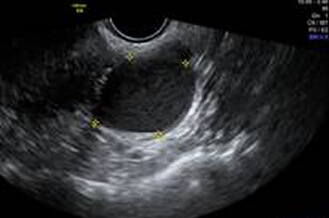

正常な卵巣